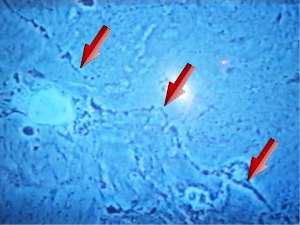

Un mécanisme particulier qui ne laisse pas de trace comme le montre la photo d'un axone s'évaporant de la sorte : il y avait à la pointe des flèches rouges un trait noir continu, trace d'un axone vivant. Processus étonnant que ce suicide cellulaire : il se déclenche par défaut en l'absence de signaux de vie. Ce mécanisme ne fait appel qu'à des éléments internes propres à la cellule (activation de gène, synthèse de protéine) contrairement à la nécrose; Ainsi un neurone qui n'est pas sollicité par ses collègues, qui ne peut établir de connexions avec ses voisins proches ou éloignés, est destiné à mourir rapidement, sans laisser de trace.